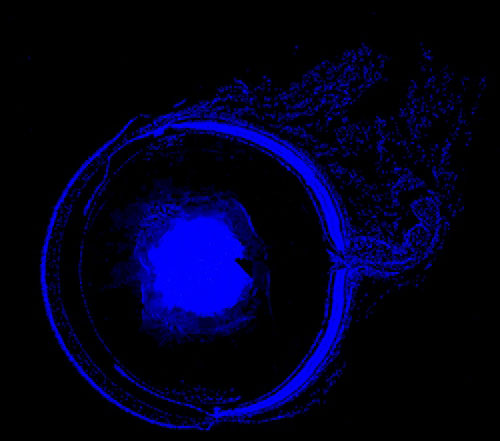

DAPI染色-小鼠眼球